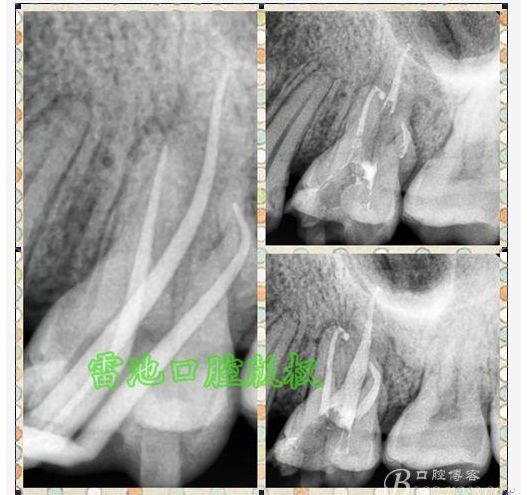

E 、X線影像學(xué)的檢查研判能力: 這點(diǎn)不需要強(qiáng)調(diào)太多,對(duì)于普通的非CBCT的二維影像對(duì)醫(yī)生讀片能力有一定的要求,有個(gè)逐步提高的過(guò)程,非一蹴而就,需要學(xué)會(huì)把二維的X線影像與三維的解剖結(jié)構(gòu)進(jìn)行良好的對(duì)應(yīng)結(jié)合,對(duì)于某些鈣化的髓室底,應(yīng)通過(guò)想象把根管口的分布、根管的走向以及各種變化通過(guò)想象投射到對(duì)應(yīng)的髓室底上;

G:找尋MB2的問(wèn)題:

1、查閱各種文獻(xiàn),MB2的發(fā)生率在52-96%之間,治療時(shí)遺漏是上頜磨牙根管治療失敗的主因,2、一般位于MB1根管口與腭根管口方向的0.5-5mm范圍內(nèi),而大多數(shù)都位于MB舌側(cè)的1-3mm處,其中2mm以內(nèi)占85.7%,3、MB1-P根管口連線與MB1-MB2根管口的連線夾角大部分(74.3%)在30度以內(nèi);4、MB2的尋找大部分需要去除相應(yīng)部位的牙本質(zhì);5、當(dāng)找到的MB根管口呈“長(zhǎng)線型”且有深色凹線向舌側(cè),或者找到的MB根管口明顯偏頰多提示有MB2的可能;6、DOM(牙科手術(shù)顯微鏡)的使用有助于找尋MB2;